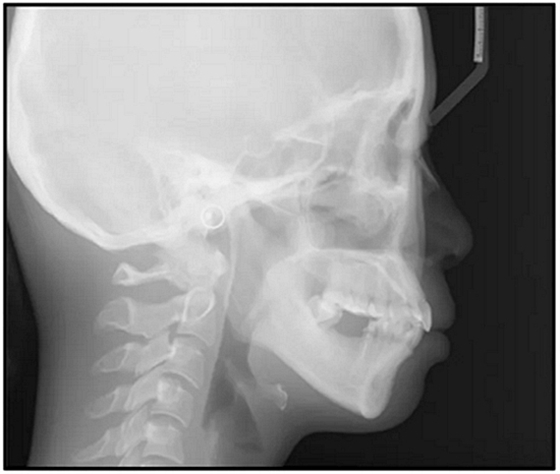

圖5. 治療前的側位片(上圖)和全景(下圖)的X光片

總之,這種復合錯合畸形是一個很嚴重的問題,需要進行認真的多學科序列治療。治療后X光片(圖6)和重疊頭影測量圖(圖7)記錄了跨學科治療結果。